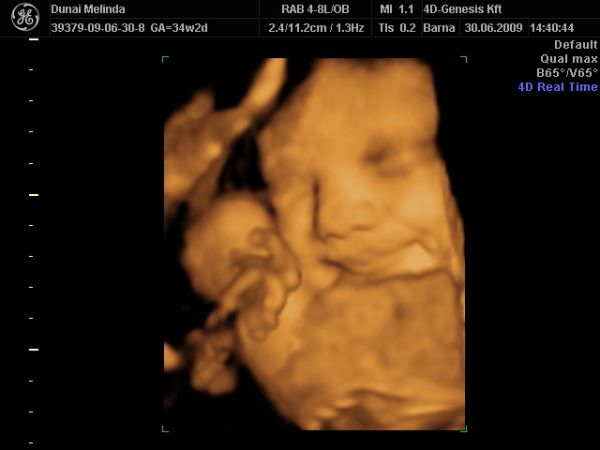

most elvileg megint vagy 10 hétig nem nézik Bogyót, 28-30. héten van megint kötelező UH. Iktass be közte egy 4D-t, ha tudsz. Én továbbra is javaslom a 4D Genesis-t, mi kedden megyünk másodjára. Olyan kedves az a nő, annyi mindent megnéz, nem csak a baba állapotát, hanem a tied is, és tuti nem enged úgy el, hogy ne hozza valahogy össze, hogy megkukkoljátok a lába közét, ha szeretnéd.

KépKép